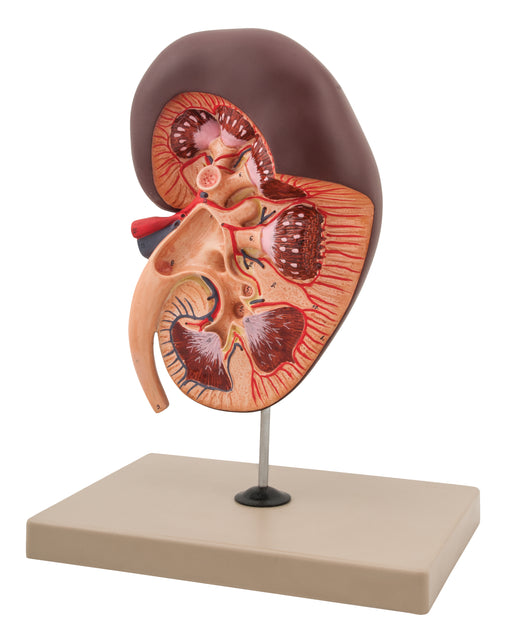

Kidney 3D With Gland

This 3d model of kidney left side showing the basic structure. Also all important parts shown. On stand, supplied with English Key Card. Size 26 x ...

View full detailsAM16058 -